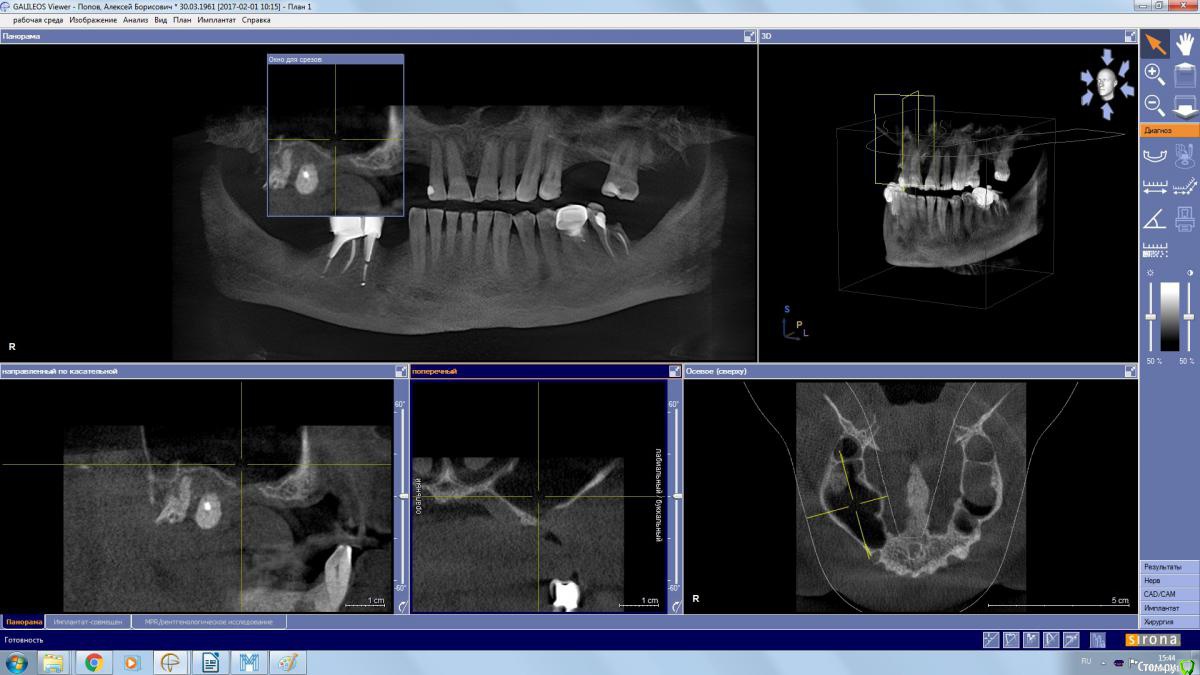

kamranchick Опубликовано 25 декабря, 2017 Автор Поделиться Опубликовано 25 декабря, 2017 (изменено) Чтобы не создавать новую тему...Пациента отправил на санацию ВЧП к лору, но вот такое дал заключение и сказал можно резать, ваше мнение? Изменено 25 декабря, 2017 пользователем kamranchick Ссылка на комментарий

red_butler Опубликовано 25 декабря, 2017 Поделиться Опубликовано 25 декабря, 2017 Другие ЛОРы по близости есть? Я бы до санации пазухи не лез. Ссылка на комментарий

Bier Опубликовано 26 декабря, 2017 Поделиться Опубликовано 26 декабря, 2017 ретенционку удали сам, через верхний доступ, этажем ниже делай синуслифт, если боишься, то в 2 этапа. Ссылка на комментарий

Irouil Опубликовано 27 декабря, 2017 Поделиться Опубликовано 27 декабря, 2017 Имхо не ретенционная, соустье вероятно перекрыто. Ссылка на комментарий